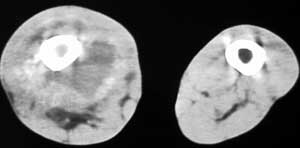

男56涨疼5-6月

右股骨下端包绕股骨见巨大软组织肿块,密度部俊,周围见瘤骨,下端骨皮质侵蚀变薄,骨质周围无骨膜反应, 考虑右股骨软骨肉瘤。

右股骨下段周围软组织肿块伴钙化,相邻股骨骨皮质受累,考虑软组织来源恶性病变

右股骨下段骨肉瘤,软组织内瘤骨,软组织肿块。